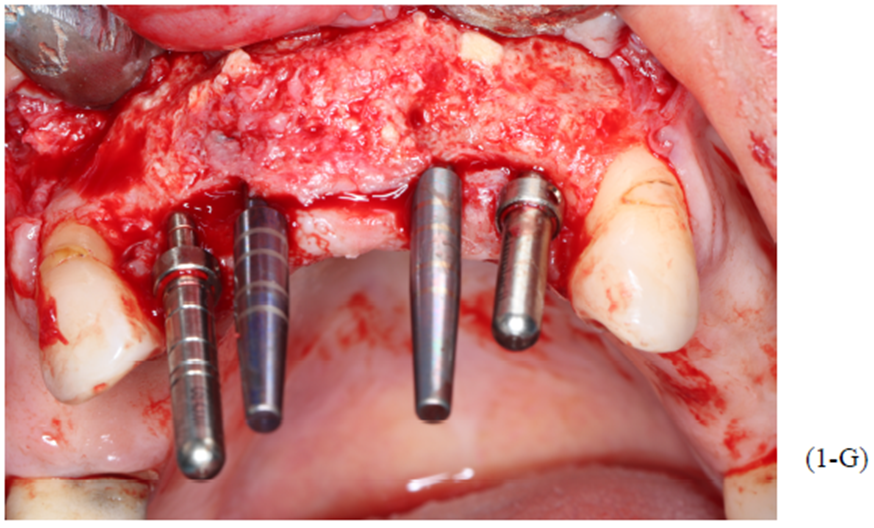

Figuras 3,4,5,6,7 e 8 – Sequência do primeiro ato cirúrgico, onde podemos observar (Figura 3) a incisão do tipo Newmann modificada para ampla visualização do campo operatório e as extrações dentárias. Podemos observar também a descorticalização do processo alveolar e a instalação dos parafusos tipo tenda Implacil De Bortoli de 10 mm, respeitando a distância de pelo menos 3 mm entre cabeças (Figura 4).

Foram colocados dois gramas de biomaterial de lenta reabsorção preenchendo toda cavidade até a delimitação da cabeça dos parafusos (Figuras 5 e 6). Antes do fechamento completo da ferida cirúrgica, colocamos membranas de PRF para auxílio na reparação tecidual e proteção do material de enxerto (Figura 7). Para fechamento da ferida cirúrgica, usamos fio do tipo Cytoplast, fornecido pela Implacil De Bortoli. É de extrema importância sua utilização, pois o fio apresenta excelente elasticidade, acompanhando edema cirúrgico pós-operatório, o que diminui o risco de deiscência no pós-operatório.

Foram planejados quatro implantes do tipo Cone Morse Maestro Implacil De Bortoli 3.5 x 11 mm. Após remoção de maneira facilitada dos parafusos tenda, foram instalados quatro implantes em ótimo posicionamento tridimensional como evidencia as Figuras 1-E, 1-F, 1-G e 1-H). Todos apresentaram estabilidade primária de 35 Ncm de torque, e aguardamos quatro meses para posterior reabilitação protética definitiva com próteses metalocerâmicas individualizadas do tipo parafusada.